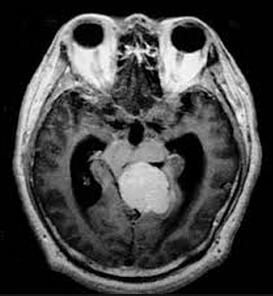

3.CT和MRI掃描 顯示顱前窩一側或雙側近中線處圓形腫瘤影像,直徑可達2.0~6.0cm,邊界清楚。CT平掃即可見高密度影,對比增強後腫瘤密度增高。腫瘤的後方可使腦室額角受壓。在MRI影像上可見腫瘤與頸內動脈的關係。